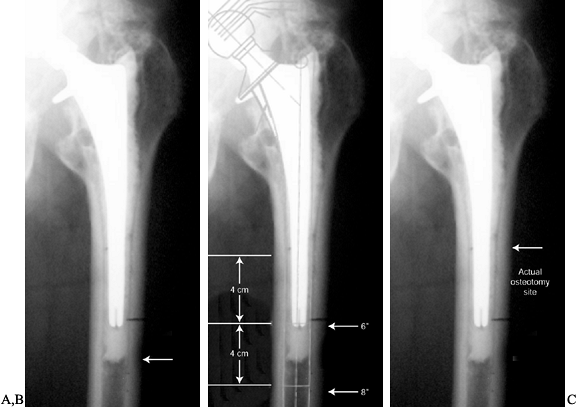

Figure 106.22. A: The arrow indicates the osteotomy site that would maximize access for cement removal. B:

The template shows fixation surfaces for a 150 and 200 mm (6 and 8

inch) component and the 4 cm minimal fixation required for each.

Placement of the osteotomy at the site in A compromises the fixation available. C:

A compromise is made, and the osteotomy is moved more proximally

because the distal cement is not well bonded and should not be

difficult to remove. -

Template the planned revision component

and check to determine whether its fixation will be compromised by the

distal extent of the osteotomy. Fully coated stems require at least 4

to 6 cm of isthmus fit (Fig. 106-22B). -

It is often necessary to shorten the

distal extent of the osteotomy so that component fixation is not

compromised. A compromise between maximizing exposure and maintaining

fixation must be reached (Fig. 106-22C).

because its location affects the choice of implant. The location of the

osteotomy is a compromise between enhancing exposure and maintaining

component fixation.

-

Plan the distal extent of the osteotomy

at the most advantageous location to accomplish the necessary task. To

remove cement, this would be at the most distal extent of the cement

mantle. To remove a porous-coated component, this would ideally be at

the junction of the metaphyseal and diaphyseal portion of the stem. An

osteotomy is also indicated when there has been varus remodeling

P.2818

of

the femur caused by a loose femoral component. Varus remodeling

prevents appropriate reaming and placement of the new component. With

varus remodeling present, the osteotomy should ideally end at the apex

of the varus deformity (Fig. 106.22A).